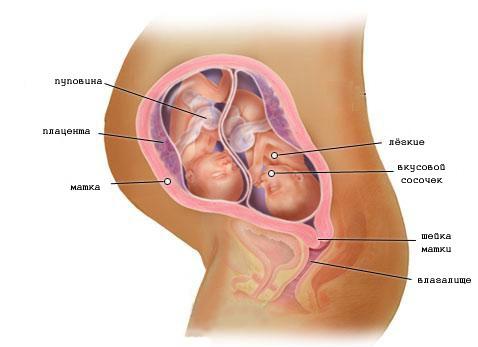

23 тиждень вагітності двійнятами

Тіла Ваших малюків стають більш пропорційними, а малюки набирають вагу. Їх підшлункова залоза функціонує, вже почалося виробництво інсуліна.Пушковий волосся темнеет.В кишечнику з'являється перший кал, (називається меконій).

Ваші малюки набрали практично по півкілограма ваги. У них поки ще дуже мало шансів на виживання при передчасних пологах, але вже через місяць вони будуть цілком життєздатні.

Здоров'я майбутньої мами двійні. Поради по 23 тижні вагітності.

На прийомі гінеколог пальпирует (обмацує) Ваш живіт. Це робиться для визначення позиції. Так називають одну з характеристик, що визначають розташування малюків у Вашій черевної порожнини. Крім того, сантиметровою стрічкою вимірюється висота стояння дна матки. Як вже говорилося, дно матки - це сама верхня її частина (звід). Вимірювання цього показника дозволяє судити про темпи зростання малюків. Попереджаючи Ваші хвилювання з приводу "занадто маленьких" або "занадто великих" змін цих показників, треба сказати, що припустимі деякі відхилення. Про неприємні моменти Ваш гінеколог обов'язково б Вас повідомив. Все ж для повного Вашого заспокоєння задайте йому це питання.